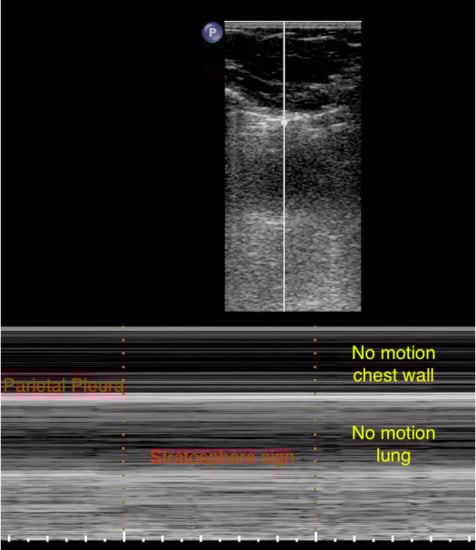

Pneumothorax

Patterns in the LUS Examination